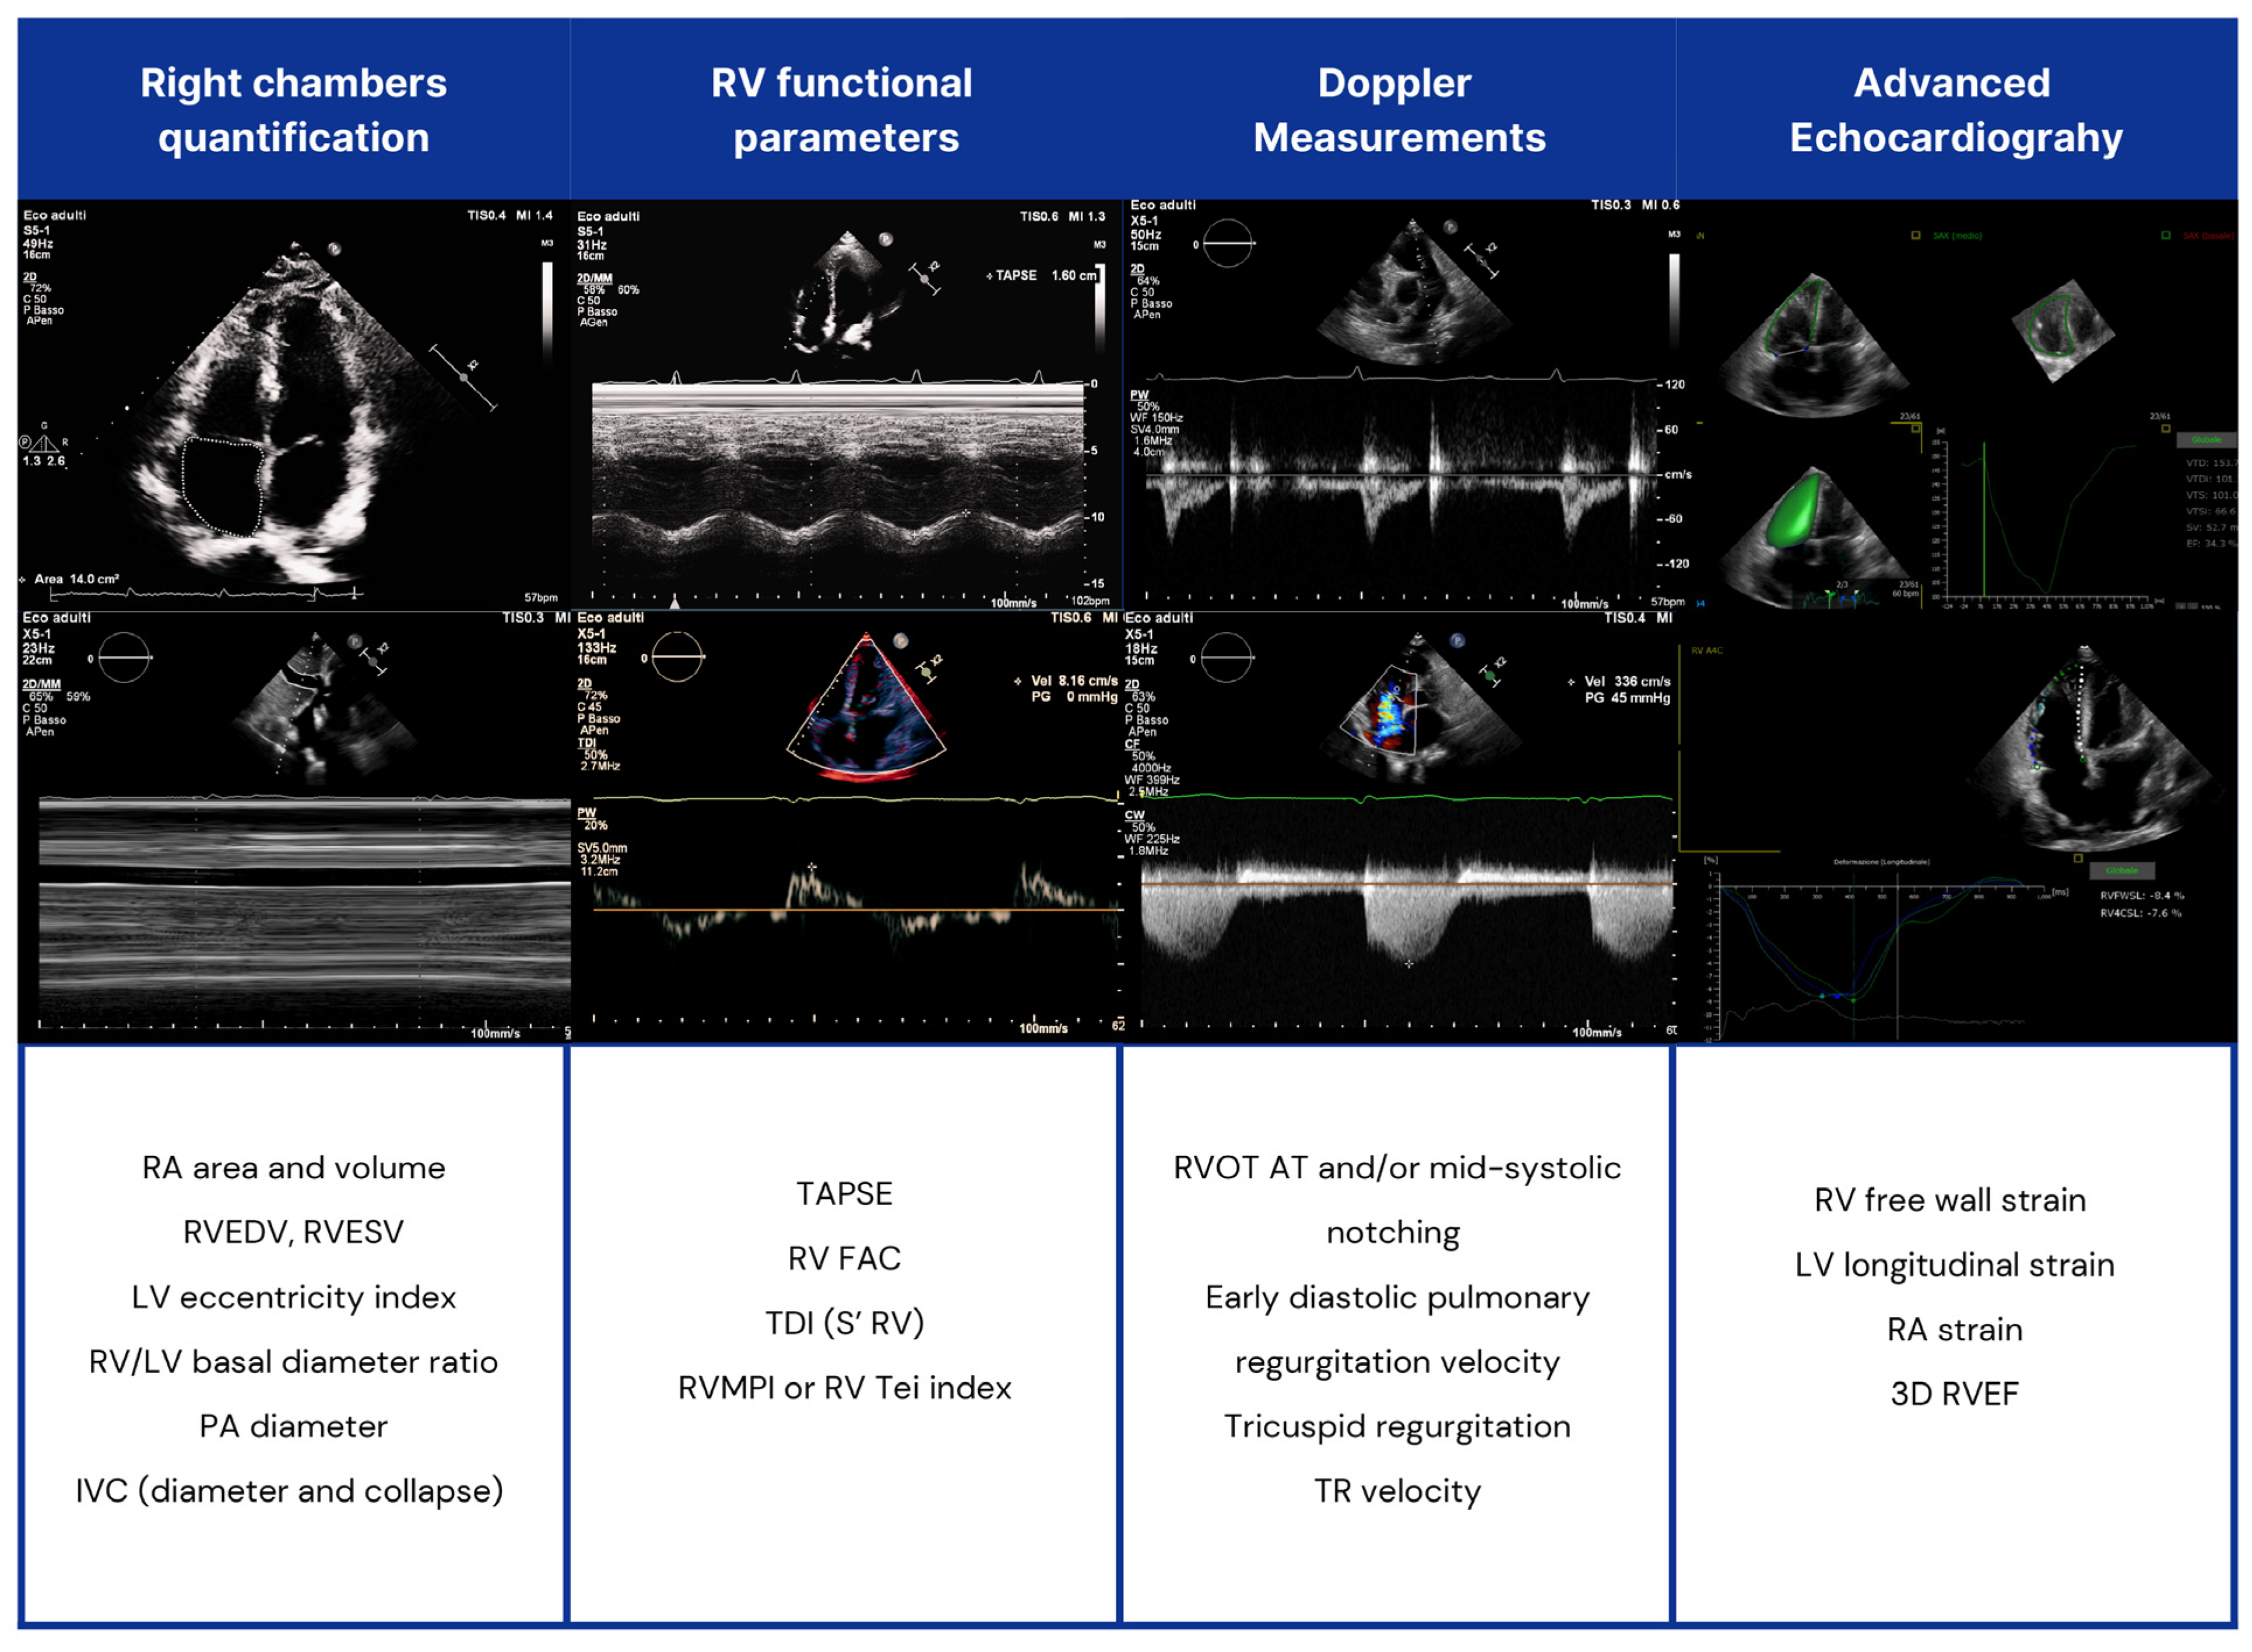

Figure 3.

Echocardiographic assessment of right heart chambers in SSc patients. RV: right ventricle; LV: left ventricle; RVOT AT: RV outflow tract Doppler acceleration time; RA: right atrial; IVC: inferior vena cava; TAPSE: tricuspid annular plane systolic excursion; TDI: tissue Doppler imaging; PA: pulmonary artery; FAC: fractional area change; RVMPI: RV myocardial performance index; RVEDV: right end-diastolic volume (RVEDV); RVESV: end-systolic volume; RVEF: RV ejection fraction (EF).